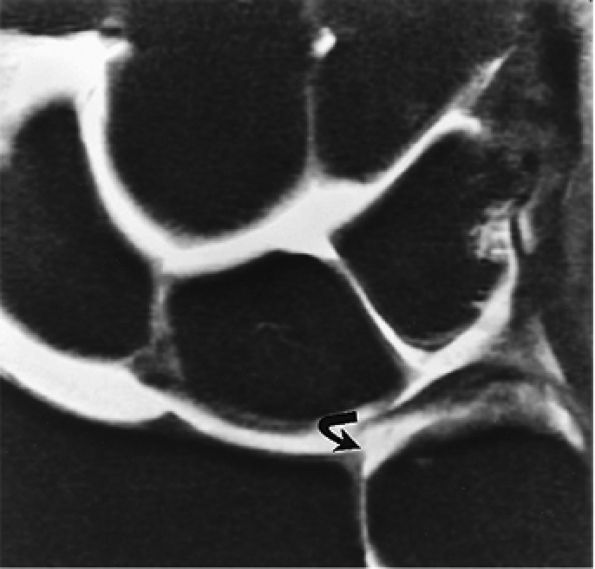

FIGURE 10.3 ● Identification of the dorsal fibers of the scapholunate and lunotriquetral ligaments on a coronal T1-weighted arthrogram. Although MR arthrography is frequently performed with FS, this decreases signal-to-noise. Routine FS PD FSE sequences are still used when performing MR arthrography, usually in the coronal and axial planes, to evaluate muscle and tendon pathology, chondral abnormalities, subchondral marrow edema, and noncommunicating ganglions. Postarthrogram sequences limited to FS T1-weighted sequences alone are inadequate for comprehensive diagnostic assessment.